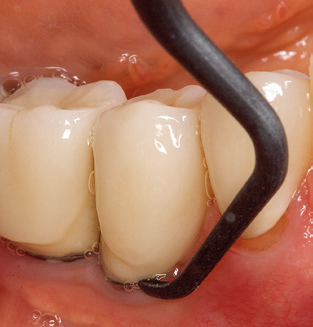

Of course, working tips for the cleaning of implant surfaces are also indispensable for SPT in patients fitted with implants. The implant cleaning attachment on the system used here is characterised by its tapered, hexagonal design. This design allows light, atraumatic penetration of the peri-implant pocket and displays a good cleaning performance (Fig. 7).

Fig. 4: Flexible probes with millimetre markings are recommended for the probing of dental implants (e.g. Colorvue Kit PCV11KIT6, Hu­Friedy). – Fig. 5a and b: A straight working tip (1P, W&H Dentalwerk Bürmoos GmbH) is a suitable instrument for use on all natural teeth. – Fig. 6: Curved working tips (3Pr/3Pl, W&H Dentalwerk Bürmoos GmbH) lend themselves to the processing of difficult-to-reach areas of the tooth and root surfaces (e.g. furcations). – Fig. 7: The tapered, hexagonal implant cleaning tip (1I, W&H Dentalwerk Bürmoos GmbH) permits atraumatic and efficient cleaning of the crown and abutment surfaces. – Fig. 8: Titanium and carbon curettes are suitable instruments for the manual cleaning of the implant surfaces.